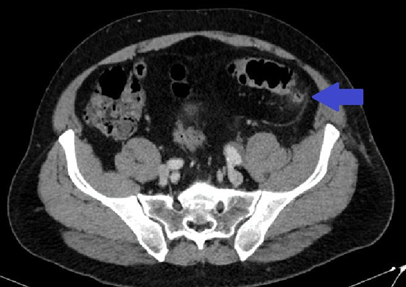

A 56-year-old man presented to the emergency department with a one week history of abdominal pain in the left lower quadrant with irradiation to the same side lumbar area. On the physical abdominal examination, he had localised tenderness in the left iliac fossa. Laboratory results showed white blood cell (WBC) count of 9.12 10e3/µL (4.00 - 12.00) and a C reactive protein (CRP) of 14.2 (<=5). A computed tomography (CT) scan was performed, which informed findings suggestive of epiploic appendagitis and multiple diverticula in the sigmoid colon (Figures 1, 2). The patient was sent home with conservative treatment.

Figure 2 Inflammatory appearance changes at the level of the epiploic appendage adjacent to the sigmoid colon. Coronal plane.